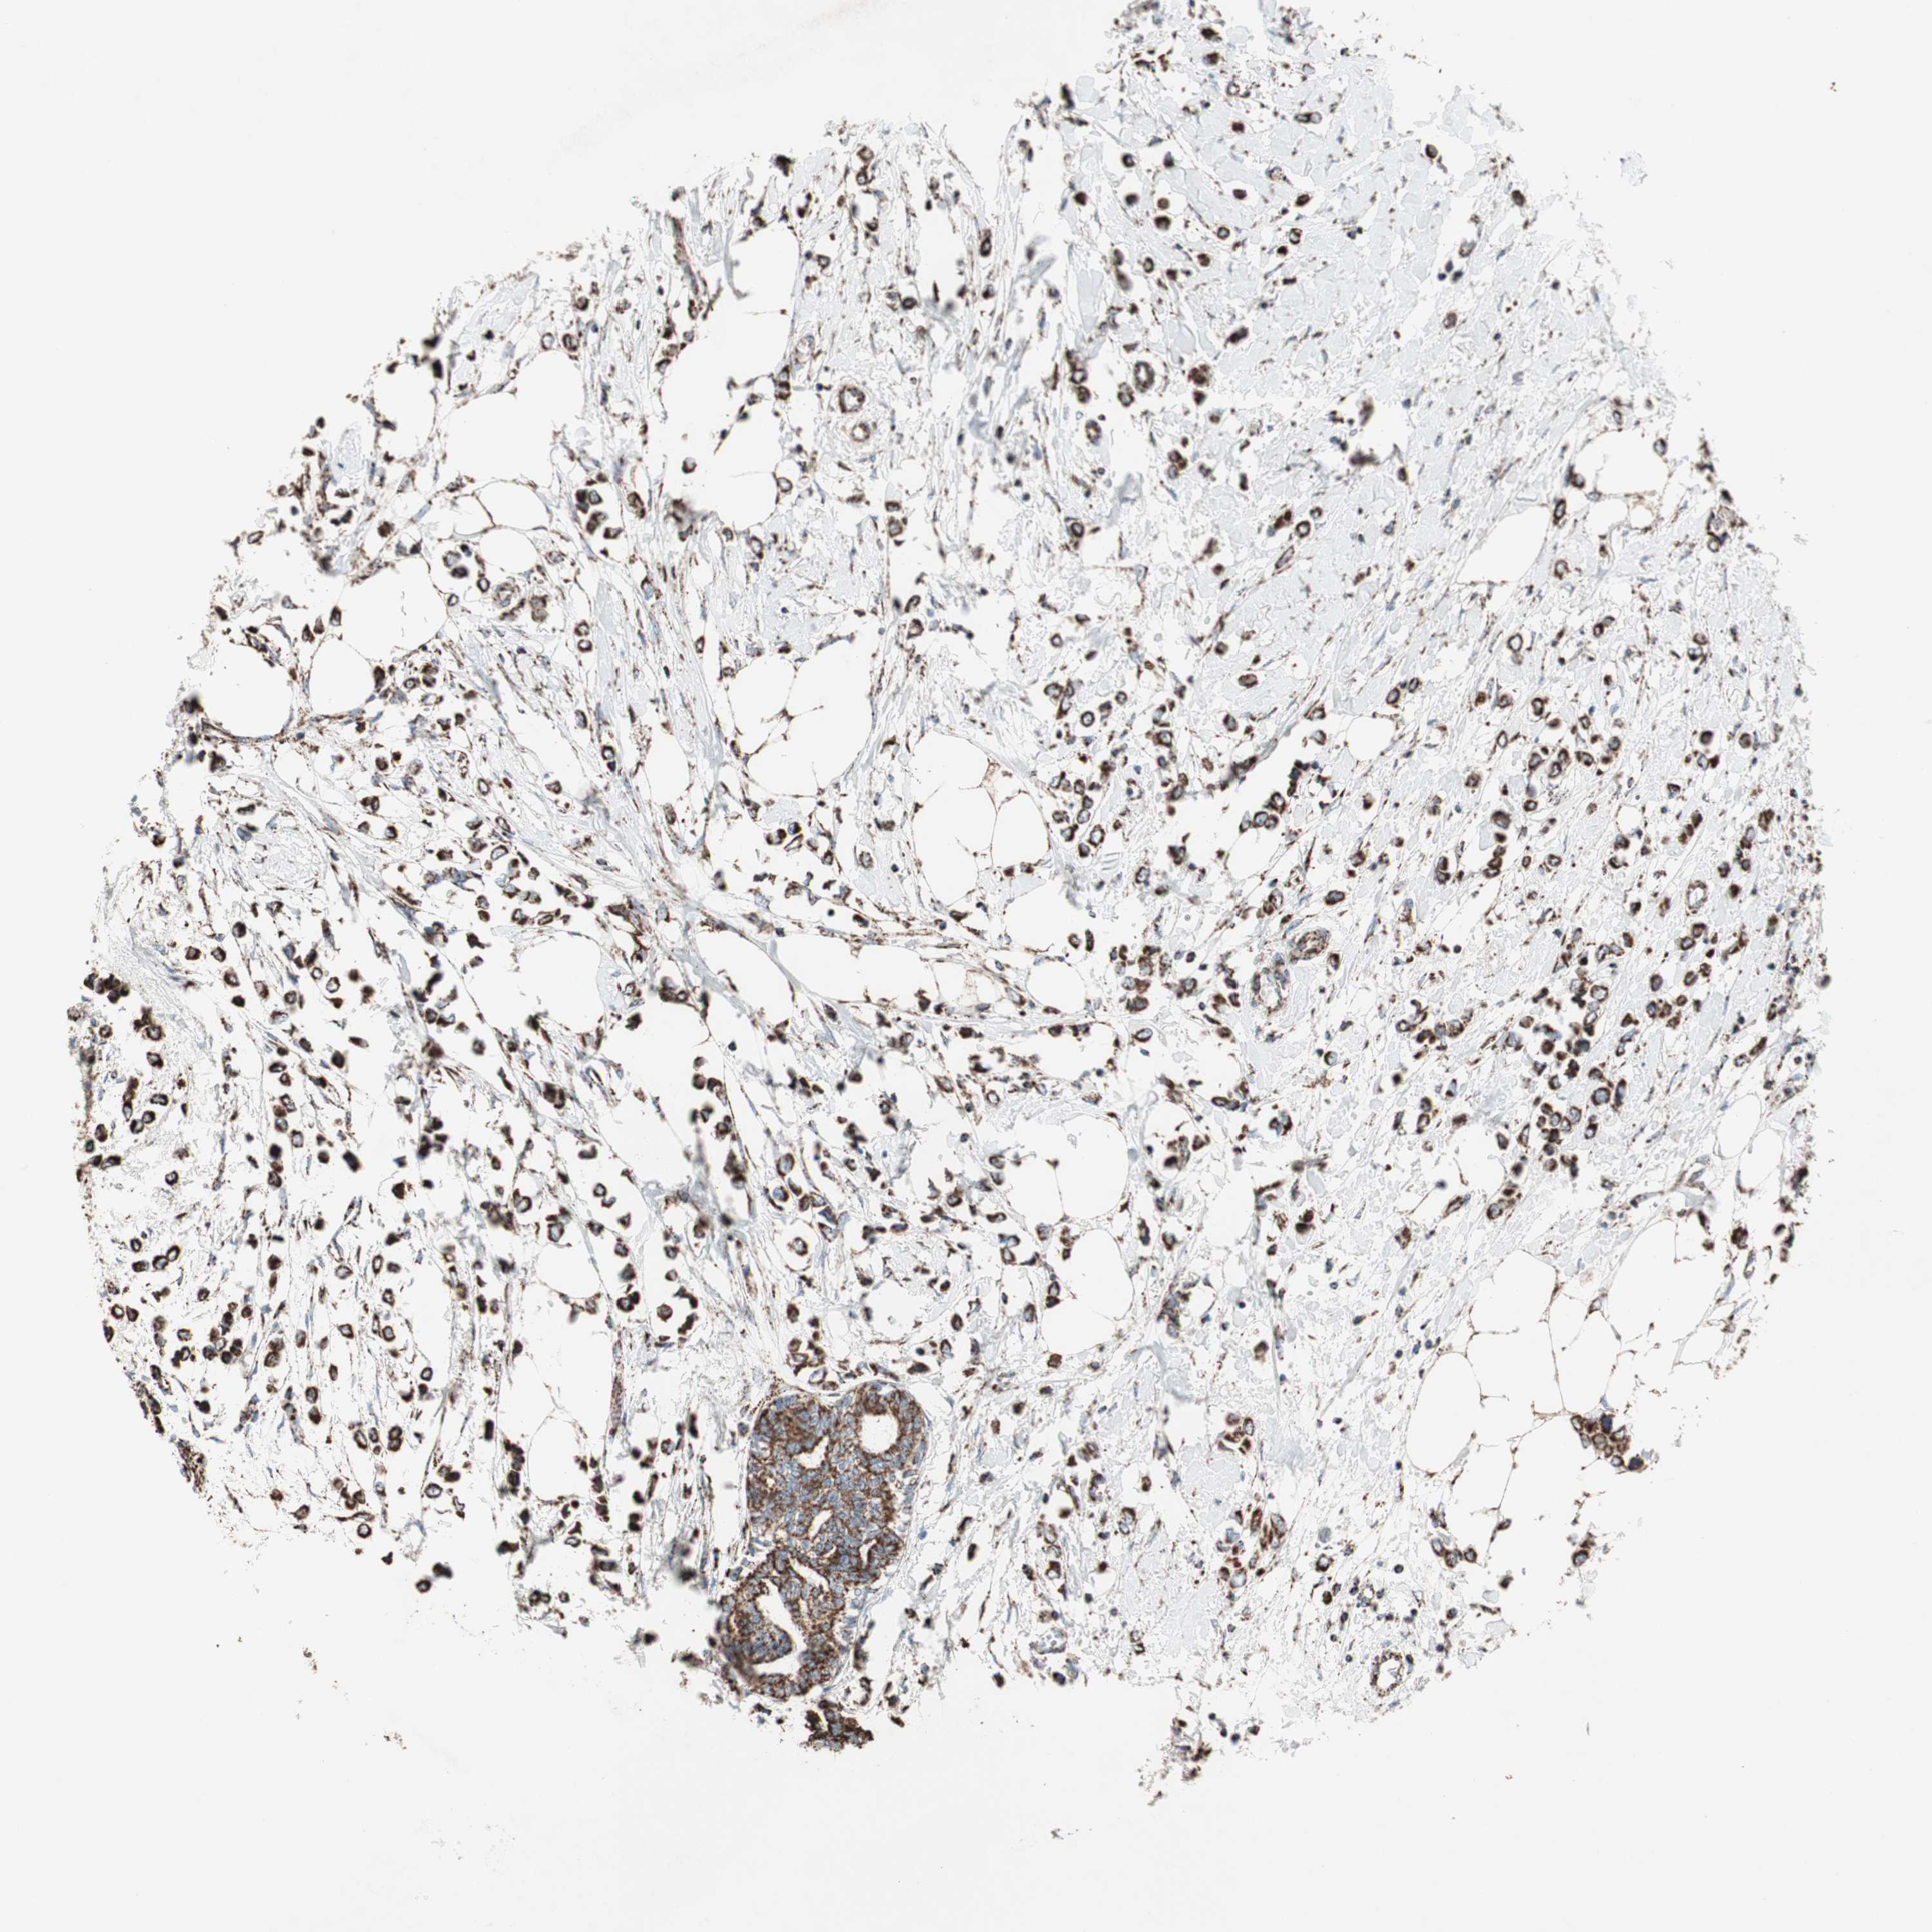

CANCER BREAST CANCER Show tissue menu

BRCA TCGA BRCA VALIDATION PROTEIN EXPRESSION

ANTIBODIES

AND

VALIDATION